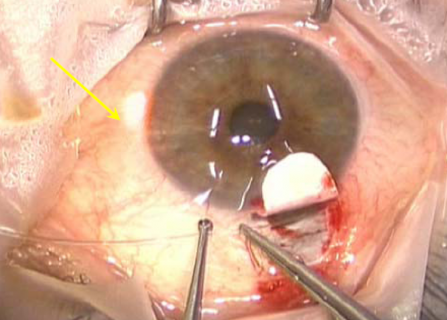

- SC is located and unroofed. A paracentesis is created. The microcatheter is advanced 360° around SC. The optical fiber that illuminates the tip of the microcatheter provides guidance to the path of the catheter as it is advanced. Figure 11

- When the distal tip of the catheter re-emerges at the surgical site, a 9-0 polypropylene (Prolene) suture is tied to it Figure 12 and the microcatheter withdrawn through the canal. Figure 13 Every 2 clock hours a precise aliquot of OVD is injected into SC via the screw driven injector. Care is taken to keep the catheter in perpetual motion through SC when OVD is injected to prevent the creation of a Descemet detachment. The microcatheter pulls the Prolene suture around the canal after it.